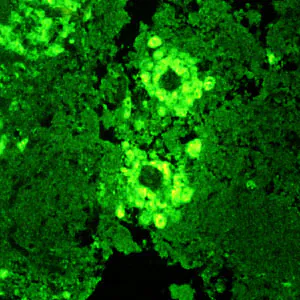

Indirect immunofluorescence (IIF) assay for free-living amebic infections.

Acanthamoeba spp.: Acanthamoeba infection can be diagnosed by detection of trophozoites and cysts on microscopic examination of stained smears of biopsy specimens (brain tissue, skin, cornea) or of corneal scrapings. Lactophenol blue, acridine orange, silver, and calcofluor white stains have been used in the diagnosis of acanthamoebiasis on histologic sections and environmental samples (i.e. pelleted contact lens case contents). In granulomatous amebic encephalitis cases, trophozoites and cysts are only rarely found in the CSF. Acanthamoeba can be cultured from clinical and environmental samples in the laboratory on non-nutrient agar with a Page’s saline and Escherichia coli overlay.

Confocal microscopy or cultivation of the causal organism, and its identification by direct immunofluorescent antibody, may also prove useful. When there are large numbers of cysts and/or trophozoites, as in very severe cases, diagnosis may be possible through direct microscopy on corneal scrapings or contaminated surfaces (i.e. contact lens cases). An increasing number of PCR-based techniques (conventional and real-time PCR) have been described for detection and identification of free-living amebic infections in the clinical samples listed above. Such techniques may be available in selected reference diagnostic laboratories.

Balamuthia mandrillaris infection is generally diagnosed post-mortem. Outside of molecular detection via PCR and recently, metagenomic deep sequencing, B. mandrillaris is most reliably detected via immunofluorescence or immunoperoxidase staining of tissue samples.